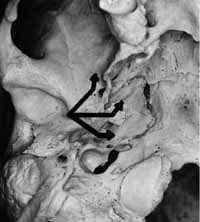

Myers (112) en 1988 sugiere que en articulaciones con discos luxados se genera inflamación crónica (113) por daño vascular, que produce edema, extravasación vascular y fibrosis, que se extiende a áreas vecinas por patrones de menor resistencia asistida en la actividad de las masas musculares, especialmente áreas mediales y anteromediales a la ATM (Figura 3). Cuando el edema toma el área anteromedial que está entre los músculos pterigoideo interno y externo, puede afectar por compresión inflamatoria el nervio alveolar, lingual, cuerda del tímpano y la arteria meníngea media.

Desórdenes inflamatoriosFigura 3. Posibles trayectorias inflamatorias de desórdenes inflamatorios de la ATM. 1- Antero medial. 2- Medial anterior. – 3- Medial posterior.

Modificado de: Myers LJ, DDS. Possible inflammatory pathways relating temporomandibular joint dysfunction to otic symptoms. The J Craniomand Prac. January 1988, Vol. 6(1): 65-70.

Cuando el edema se desplaza al área medial, puede tomar dos patrones: uno va más posterior rodeando el proceso estiloideo siguiendo los tejidos faciales distal y caudalmente al área de la arteria carótida interna, la vena yugular y los nervios hipogloso y glosofaríngeo (región de la vaina carotídea). En este segundo patrón dirigido a la vaina corotídea se genera fibrosis y adhesiones, lo cual produce tensión en ésta con los movimientos de la mandíbula y del cuello. Esta tensión se transmite al foramen yugular y al saco endolinfático que genera presión endolinfática a las células ciliadas de la cóclea que puede generar tinnitus y vértigo.

El tercer patrón descrito pasa entre el origen del músculo elevador del paladar y el tensor del velo del paladar, formando un espacio con el ápice del istmo de la trompa de Eustaquio permitiendo que el edema y la fibrosis se dirijan hacia ésta en su zona más vulnerable (istmo) por ser la más estrecha, que puede ser presionada, cerrando la luz del istmo y generando síntomas óticos de plenitud y otitis media.

Myers demuestra la fragilidad de las extensiones extraóseas del oído medio en la trompa de Eustaquio y del oído interno en el saco endolinfático. Sugiere que el Síndrome de Ménière (incrementó de la presión endolinfática) que involucra la pérdida auditiva transitoria o permanente, tinnitus y vértigo tenga una explicación etiológica en esta teoría.